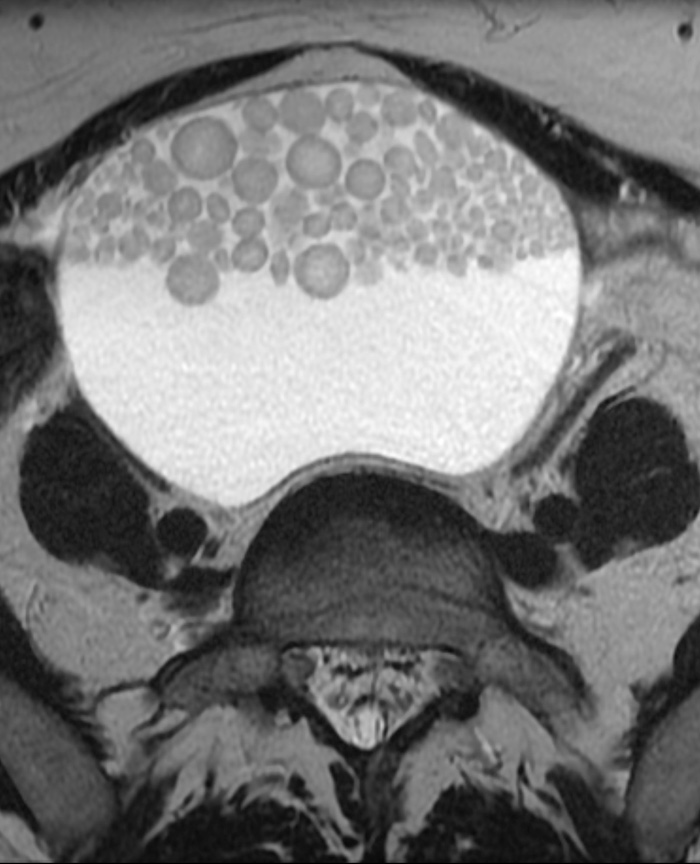

Perler i en ovariecyste

Ovariale dermoidcyster påvises og karakteriseres som regel ved transvaginal ultralyd. MR- eller CT-undersøkelse benyttes i noen tilfeller for preoperativ verifisering ved å dokumentere innhold av fett, eventuelt fett/væske-speil (1). Slike funn er diagnostiske for dermoidcyste, men tilstanden kan noen ganger ha en uvanlig presentasjon.

En kvinne tidlig i 40-årene var henvist til MR-undersøkelse av lille bekken for karakterisering av ovariecyster. To cyster på ca. 5 – 6 cm inneholdt fett. Aksialt T2-vektet bilde (se bilde) viste en større cyste på 15 cm som inneholdt væske og multiple antideklivt beliggende, solide kuler. Disse var av varierende størrelse, men ellers ganske ensartede. Slike kuler kan – når de er til stede – ha et karakteristisk utseende ved ultralyd (floating intracystic balls) og regnes som patognomoniske for dermoidcyster (2). De består vesentlig av talg og keratin. Sentralt finnes gjerne et nidus, eksempelvis et hårstrå. Det er nærliggende å sammenlikne utviklingen av disse kulene med danningen av en perle i en musling.